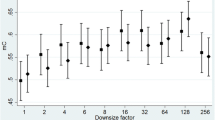

In most studies, texture analysis has been performed within a single ROI in the breast (Table 1). This single ROI is usually placed in the retroareolar breast area, while, in some cases, it can be a larger region corresponding to the entire breast or to the largest rectangular box inscribed within the breast (Fig. 1a and b). In an attempt to capture the granularity and heterogeneity of the parenchymal texture within the breast, more recent studies have estimated texture in multiple ROIs throughout the breast (Fig. 1c and d). A lattice-based strategy which splits the entire breast into multiple square patches was proposed by Zheng et al. [51, 52] showing that, with respect to single ROI methodologies, this breast sampling technique may improve risk assessment, with performance being maximized when smaller patches (6.3 × 6.3 mm2) are used. Multiple ROIs defined at various scales of breast tissue density were used by Sun et al. [53], where it was shown that fusing features from different density scales may prove to be another effective way to enhance the cancer prediction performance.